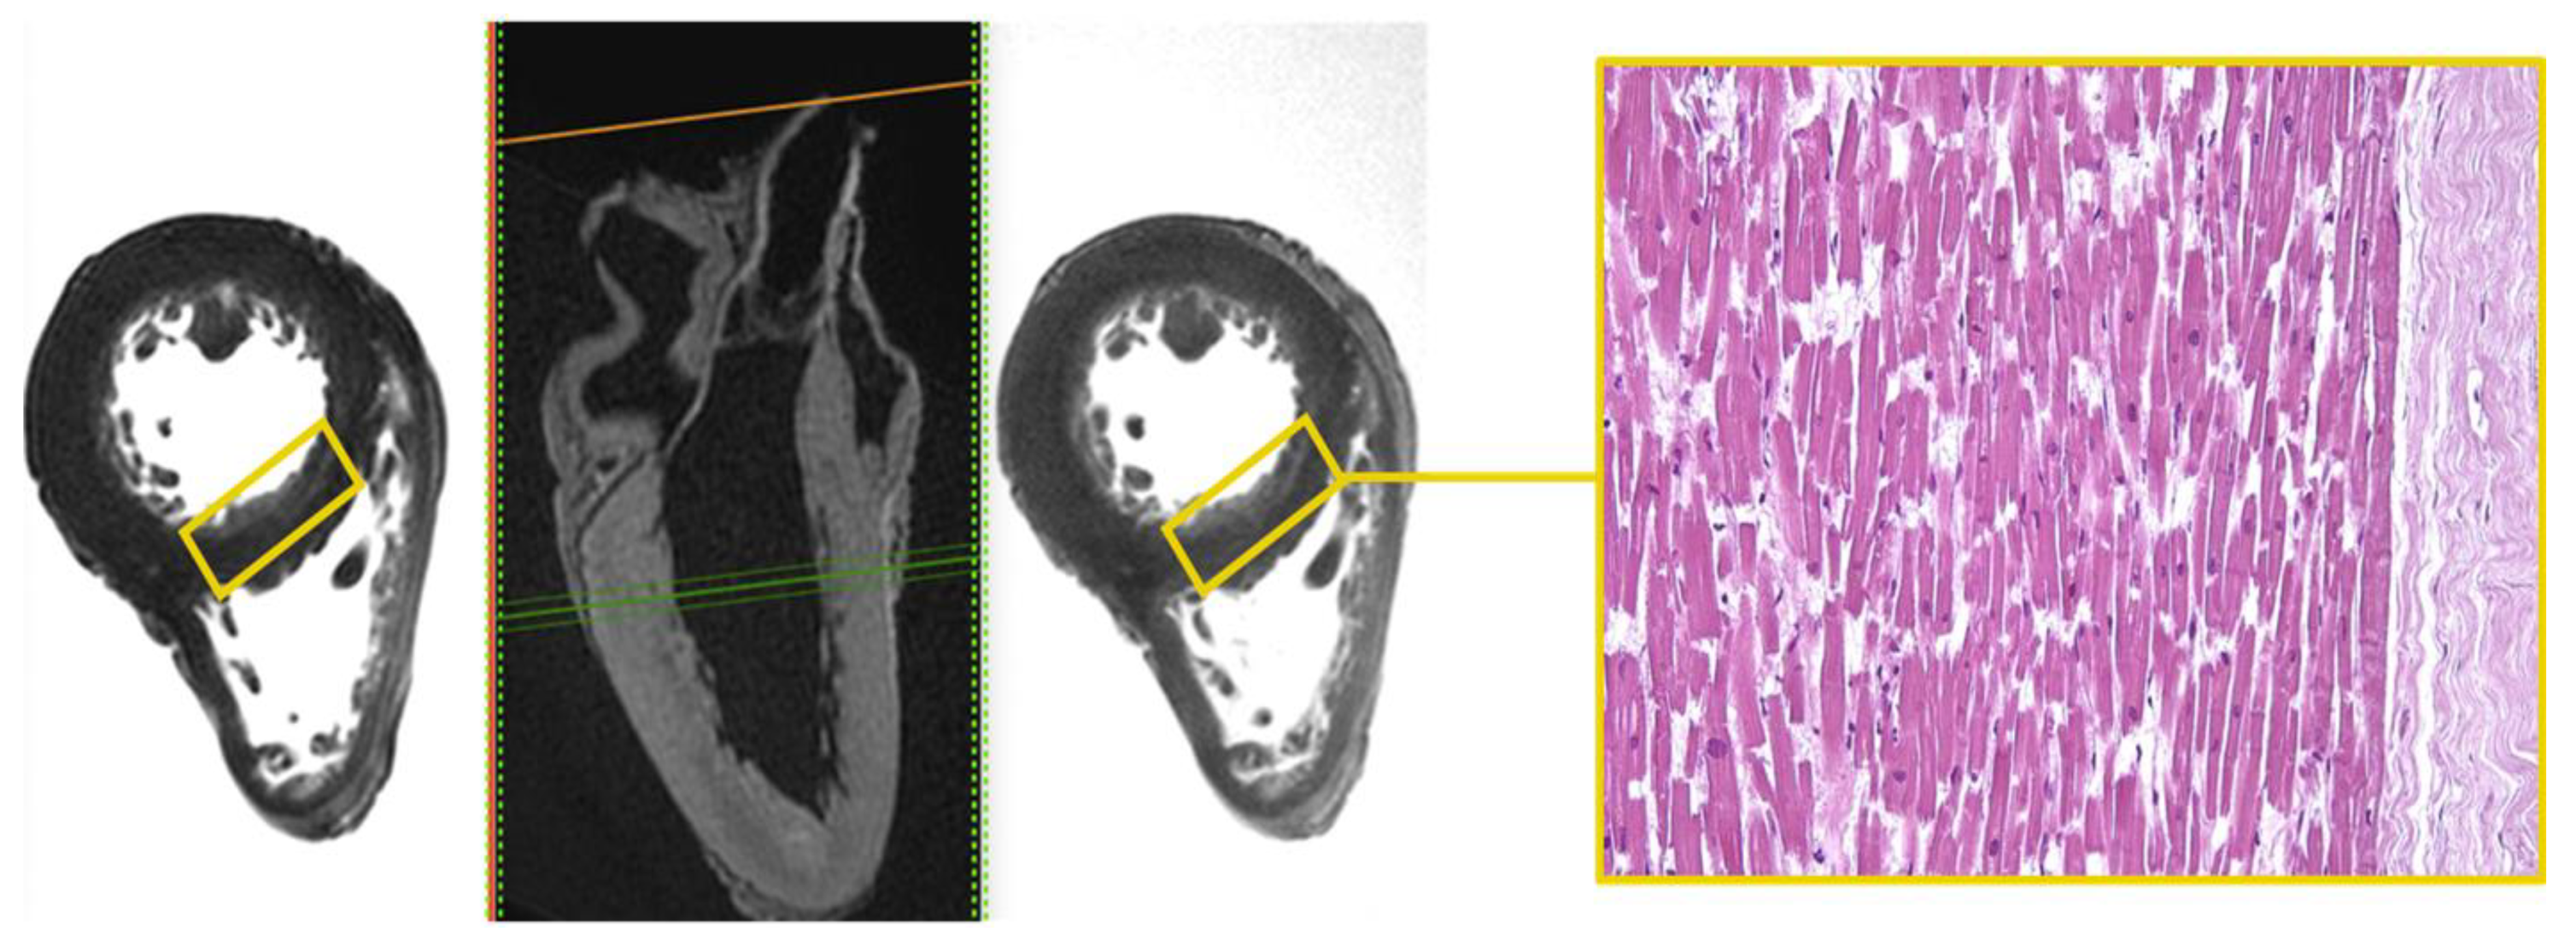

Area of altered signal, with blurred edges and hyperintense in the long TR sequence fluid-sensitive (STIR), was appreciated in the mid-cardiac level, at the sub-endocardial area of the LV septum (Figure 1).

Figure 1.

Heart C. STIR—T1-3D—T2 3D sequences. Hyperintense sub-endocardial area in STIR sequence at the mid-cardiac area at the LV septum and the corresponding histological H&E preparation in which foci of myocells characterized by contraction band necrosis, and the presence of amorphous eosinophilic material were visible (×40).

Microscopic analysis demonstrated foci of myocells characterized by sarcorexis, with transverse hypereosinophilic bands and contiguous stretched fibers, separated from each other by the presence of amorphous eosinophilic material.